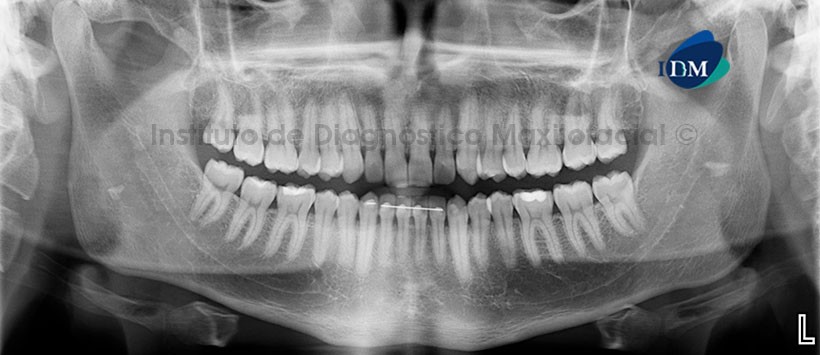

Paciente masculino, 24 años de edad, es referido al Instituto de Diagnóstico Maxilofacial (IDM) para exámenes radiográficos con motivo de control de tratamiento de ortodoncia.

En la radiografía panorámica (Figura 1) se aprecia una imagen radiopaca de densidad cálcica, forma irregular y limites definidos, proyectada a nivel de la rama mandibular derecha, se aprecia además su respectiva imagen fantasma en el lado contralateral de la rama mandibular.